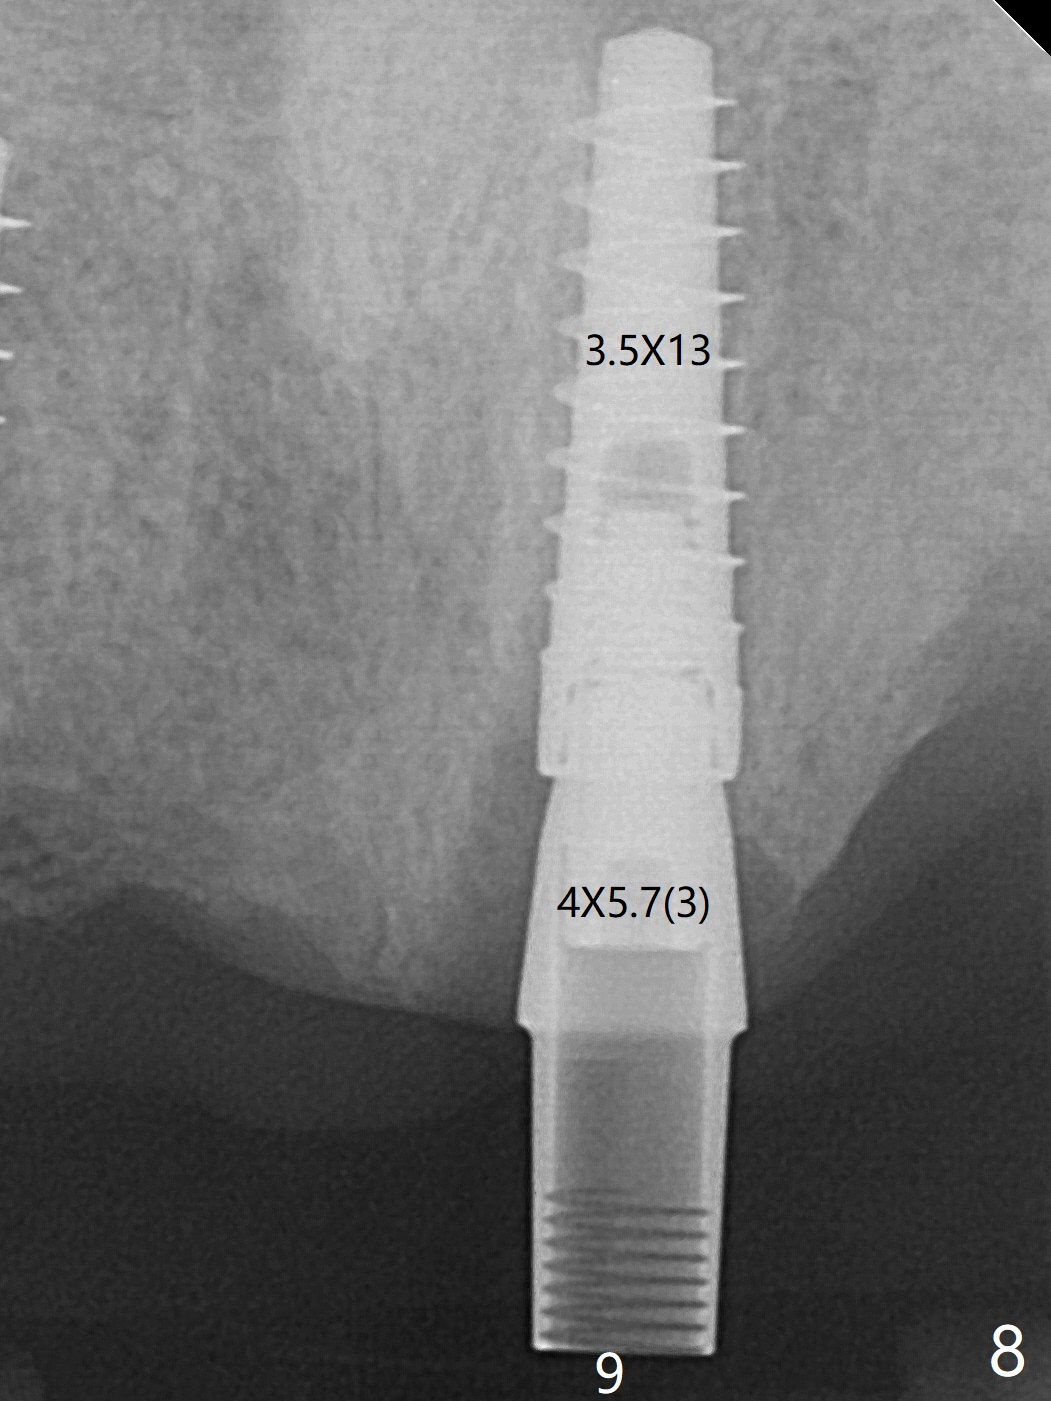

今天下午进入治疗室,粘性骨粉已制备:上清液来自红管(含促凝剂),离心3分钟(图一);再离心10分钟上清液就转变PRF,压制后,使用前剪成三块(图二:黑线),其中两块punch一个洞(图二:圆圈),插入7,9号牙基台固定;大块覆盖11/12号牙牙槽窝(图十四)。7,9,11,12号牙必须拔除(图三),然后在7,9,12种植。由于缺失左下磨牙,前牙垂直距离减少(图四)。完成9号牙位钻洞后,利用fixture mount(图五:M)植入植体,并留在原位固定导板(图六),然后7号牙种植,也留下fixture mount(图六:7,9),最后完成12号牙植入,但是后者扭力低,放置愈合螺帽(图九),而7,9号牙位放置修复基台(图七,八(使用5.5毫米profile drill后),好像基台没有完全就位。7号牙位更换基台似乎没帮助(图十),9号牙位再次放置同一个基台临床上仿佛有改变(比较图八与十二)。放置粘性骨粉后(图十一至十三),牙槽窝口覆盖PRF膜(图十四:P(A:基台)),最后使用树脂敷料固定骨粉和膜(图十五,六),基台帮助敷料固位,没有咬合干扰(图十七:*)。树脂敷料部分解决美观问题,一个月后撤除,如果植体仍有稳定性,可能制作7-10临时牙桥,可能部分维持或者恢复牙龈外形。术后一周病人主诉后面植牙和鼻底疼痛,11号牙根尖牙龈充血(图十八),轻度触痛,可能与术中尚未完全清创有关(图十九(术前CT 3D图像))。再服用Amoxicillin一周,症状好转,鼻底轻度触痛(图二十)。术后1.5月没有任何不适,撤除树脂敷料,7号牙基台(袖)显得太长,换一个短的(4.5x4(5)(图十,十一)->4x4(3)毫米)毫米),植骨好像愈合正常(图二十一:*)。7号牙换了短的基台,9号牙基台高度调整后,与对合牙有足够空间做临时牙桥,最好8,10号牙位牙龈应该凹陷(图二十二:*),有pontic外形。另外9号牙基台颊侧牙龈边缘有所修整,临时牙桥准备。先做7-10临时牙桥,理想临时牙桥pontic处树脂应该多些(图二十三:白线)压迫牙龈形成凹陷。11,12号牙牙槽窝在树脂(Bosworth)敷料下也正常愈合(图二十四)。